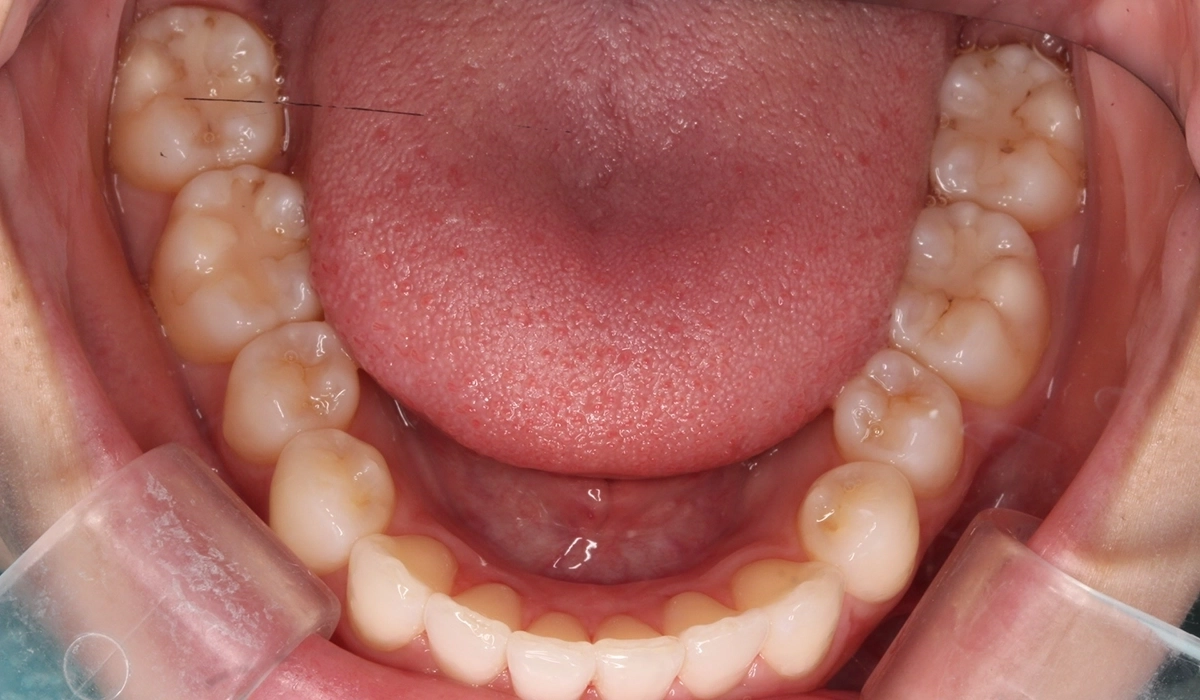

術後:上顎

術後:下顎